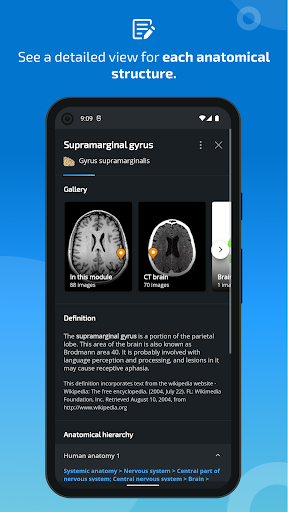

*Vista detallada mejorada de partes anatómicas para una identificación más fácil en imágenes del módulo actual y otros.

la vista de detalles de una estructura anatómica ahora se muestran los términos relacionados

-Dentro de la vista de detalles de una estructura anatómica , un alfiler ahora señala la estructura relacionada en todas las imágenes presentes

También toque directamente en la imagen para navegar a la imagen presentada en ese módulo

-Nueva opción para expandir galerías de imágenes en la pantalla de información de estructura anatómica.